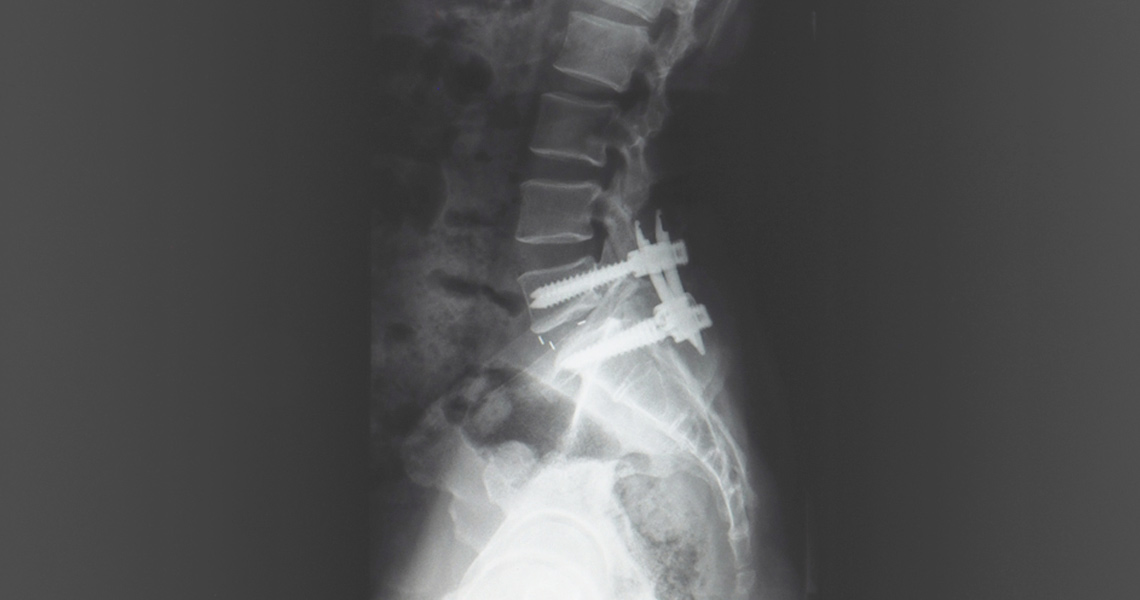

Surgical Procedure: During joint fusion surgery, our skilled surgeons use advanced techniques and instrumentation to prepare the joint surfaces, remove damaged tissue, and securely fixate the bones in the desired position. This may involve using screws, plates, rods, or bone grafts to facilitate fusion and promote healing.